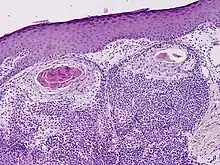

| Clear cell hidradenocarcinoma | |

Hidradenocarcinoma, also known as malignant hidradenoma, malignant acrospiroma, clear cell eccrine carcinoma, or primary mucoepidermoid cutaneous carcinoma, is a malignant adnexal tumor of the sweat gland. It is the malignant variant of the benign hidradenoma. It may develop de novo or in association with an existent hidradenoma.[1]